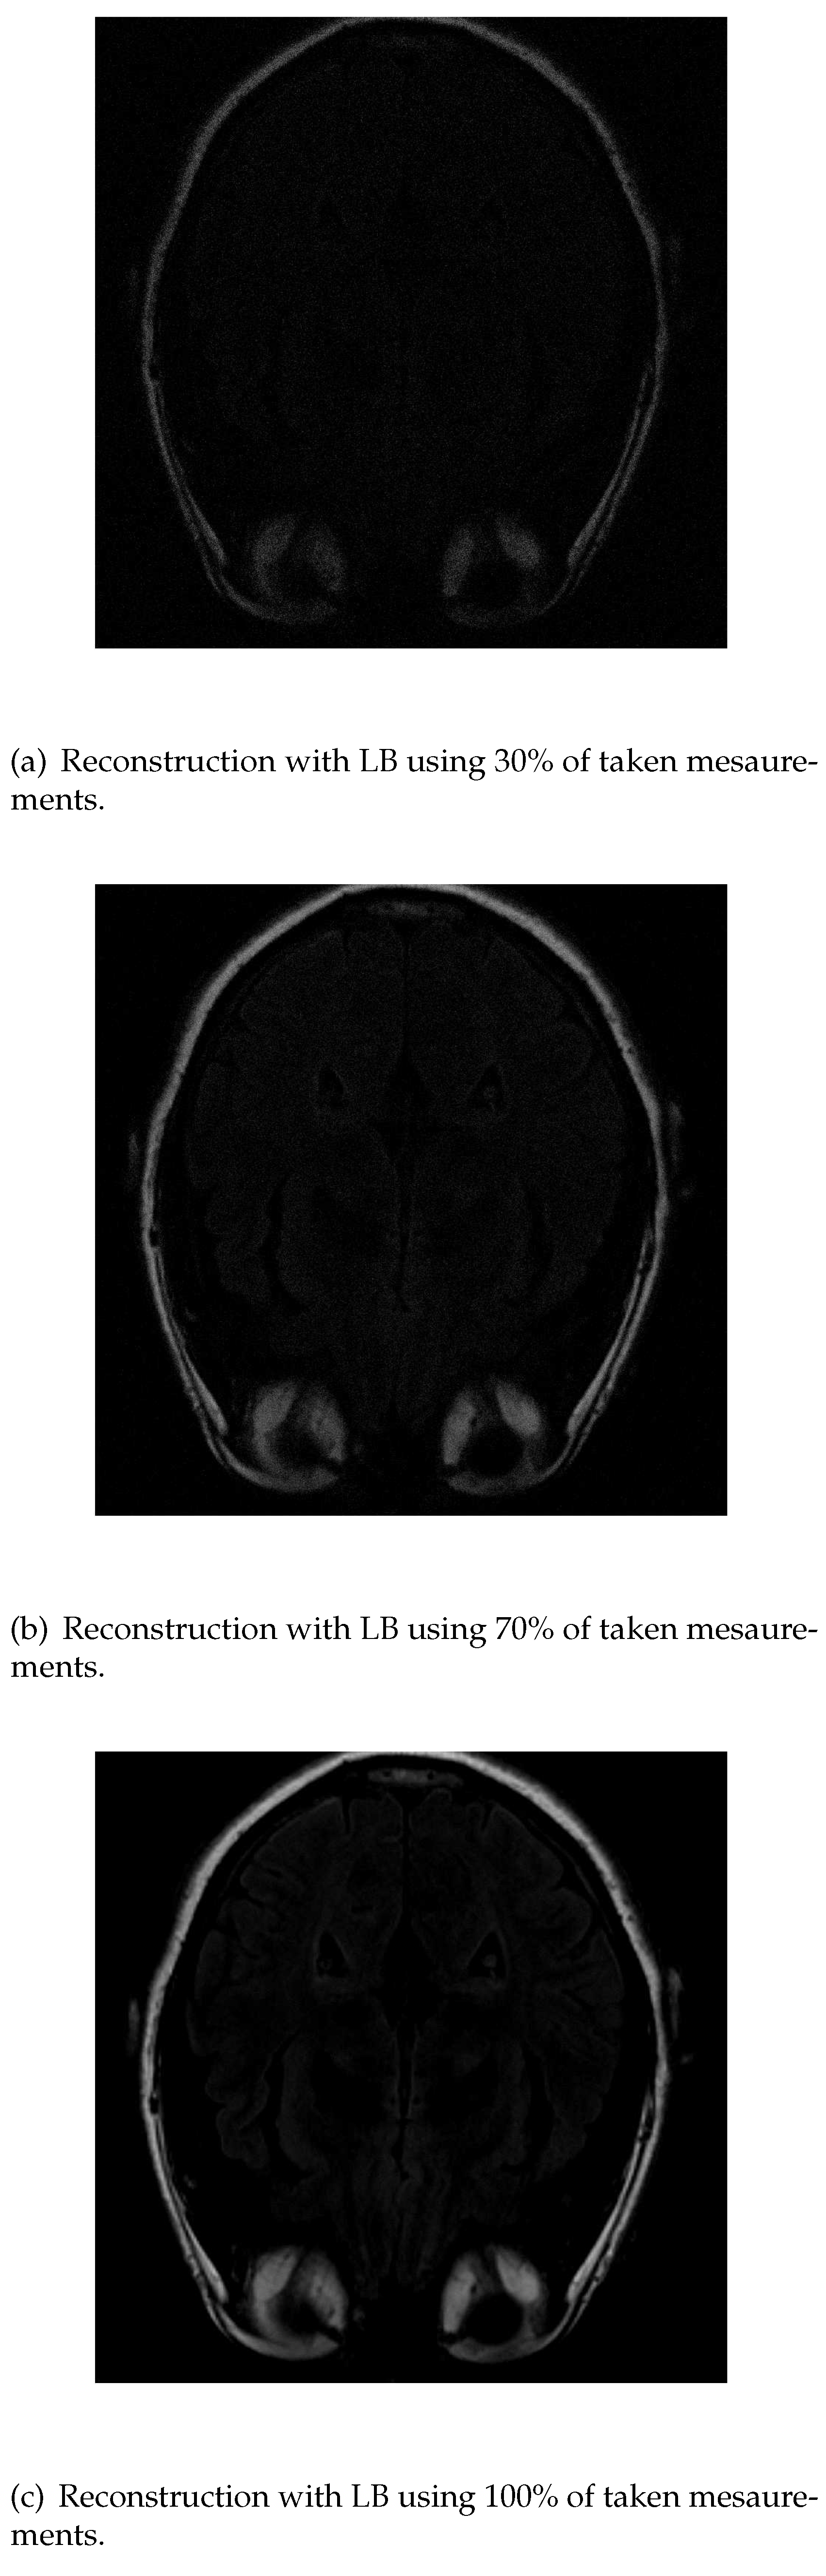

The images obtained with last algorithm, LB, are more blurred. With 30% of the measurements Figure 9a) it is not posible to distinguish the structures. It the algorithm works with 70% of the initial data Figure 9b), the image is reconstructed clearly. In the end, with all 100% of the data, the reconstruction is similar to the one obtained with PD algorithm.

Figure 9. Reconstruction of the image in Figure 3 using LB with 30 % (a), 70 % (b) and 100 % (c) of taken measurements.